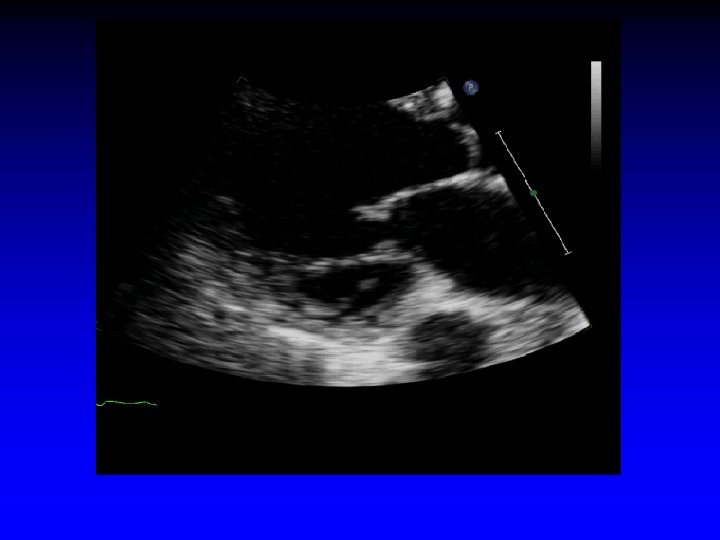

Case 7 Ischemic MR restricted PML

Bent anterior mitral leaflet

Increased tenting area